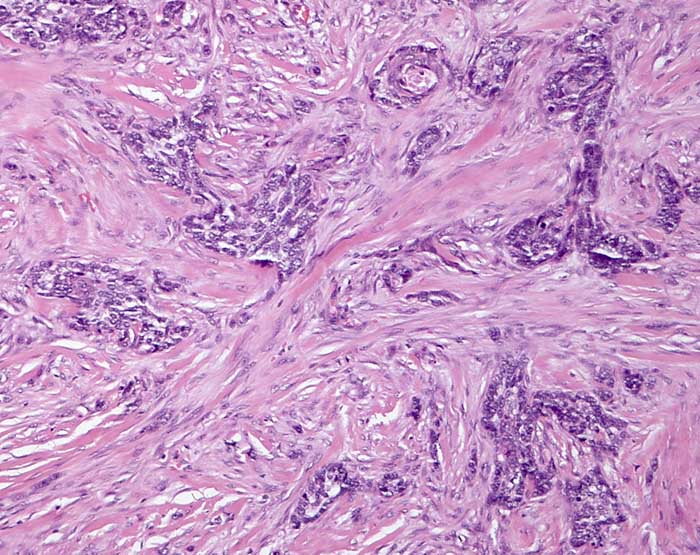

infiltratives sklerodermiformes Basaliom

Basaloide Zellkomplexe werden von reichlich desmoplastischem Stroma komprimiert.

Basaliom mit porzellanartiger weiss glänzender Oberfläche.

Dieser Tumor ist oft ausgedehnter als klinisch sichtbar. Die Schnittrandkontrolle muss deshalb intraoperativ mit Schnellschnitt erfolgen.